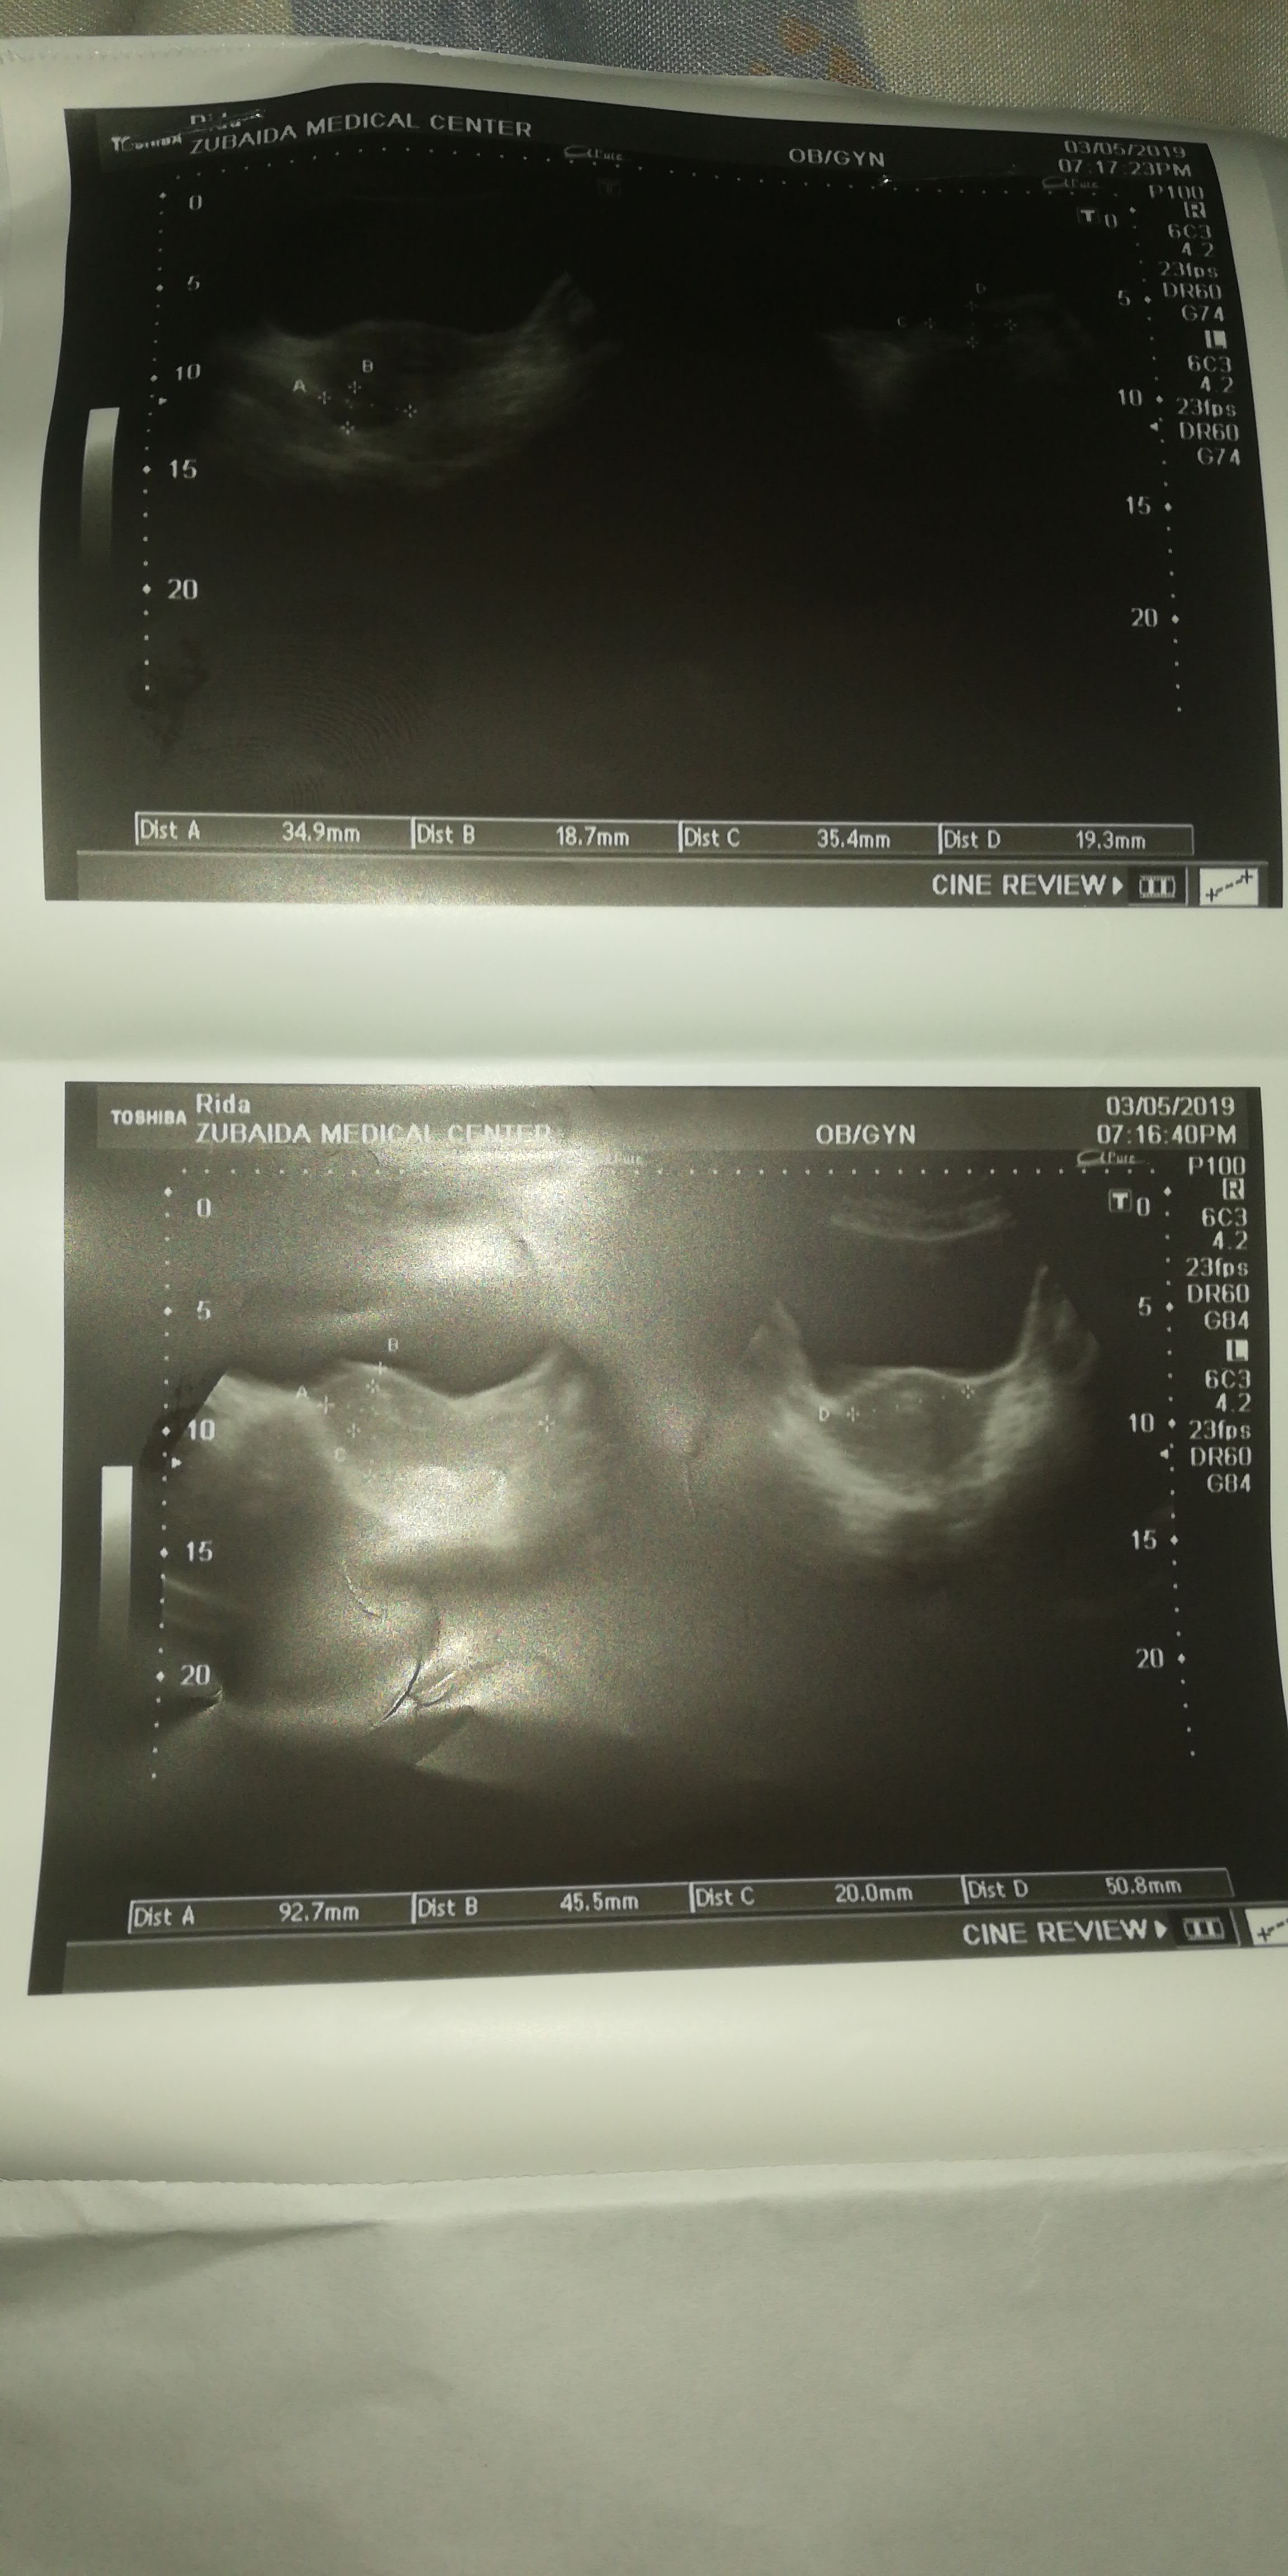

Iam facing irregular menstrual periods from March my last period was in Feb but till date no sign attached below are my ultrasound reports please can anyone let me know what is the problem and what medicine should I take for periods aur multivitamins I shall be grateful

Are u married ? U need a withdrawal bleeding , after taking harmones withthis thickness and a follow up scan , this focal thickening ca be a polyp so repeat the scan after withdrawal bleeding